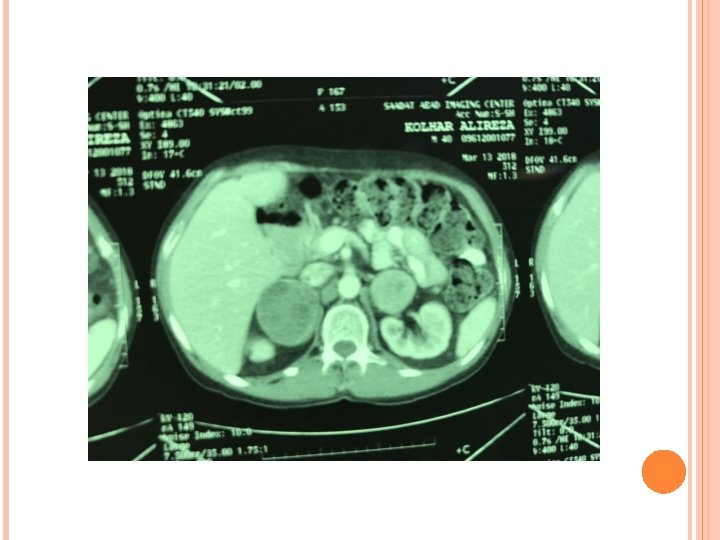

A CT of abdomen/pelvis revealed a round, heterogenous solid, 5/6 cm mass in right adrenal and 3/8 cm mass in left adrenal.